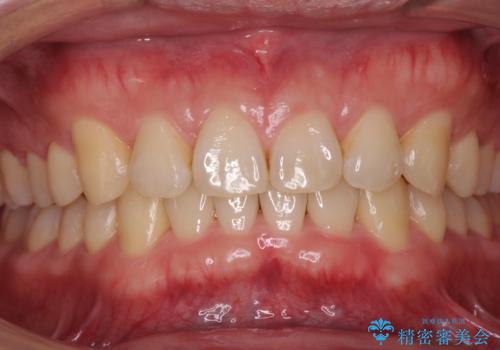

左上の奥歯がシザーバイトがありワイヤーで部分的な矯正を行い、シザーバイトを改善した後にインビザラインで全体的な矯正治療を行いました。

シザーバイトは歯と歯が噛み合っていないのでしっかり噛むように処置をする必要があります。

歯のがたつきが改善され大変満足されました。